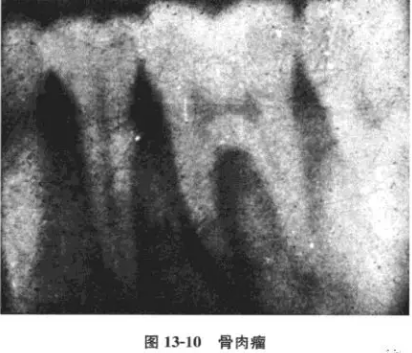

(三)骨肉瘤

病例 男性,18歲,[6極度松動,咀嚼痛伴局部腫大而就診。檢查:[6III度松動,牙髓活力測試無反應,牙周袋3~5mm,左下頜角打及3mm×3mm之腫塊,邊界尚清,質(zhì)地中等偏軟,無壓痛,x線片示:[6兩根側(cè)及根分叉對稱性牙周間隙增寬。為確診腫塊性質(zhì),轉(zhuǎn)口腔頜面外科,攝下頜骨正側(cè)位片,見左下頜角有溶骨性破壞,手術后病理診斷為骨肉瘤。

分析與述評

口腔頜面部肉瘤可分為軟組織肉瘤和骨源性肉瘤兩大類;骨肉瘤根據(jù)不同的病理表現(xiàn)又有骨纖維肉瘤、成骨性骨肉瘤、溶骨性骨肉瘤以及軟骨肉瘤等不同類型。骨肉瘤起源于頜骨中心或牙槽內(nèi)者可早期表現(xiàn)為牙松動、牙齦腫脹等類似牙周炎的表現(xiàn)。x線攝片可見牙周間隙呈帶狀(或呈平行)增寬,而且常常是近遠中同時發(fā)生。本病例因牙痛就診,牙髓活力無反應,伴牙松動及牙周袋存在,若非在其后側(cè)觸及腫塊,極易誤診為牙周病及根尖周病,或牙髓牙周聯(lián)合病變。其x線片亦表現(xiàn)為較典型的早期骨肉瘤破壞陰影(圖13-10),為此,作為牙體牙髓科醫(yī)師必須具有此基本概念和知識;更重要的是決不能忽視口腔頜面部的全面檢查,以保證診斷的正確性。